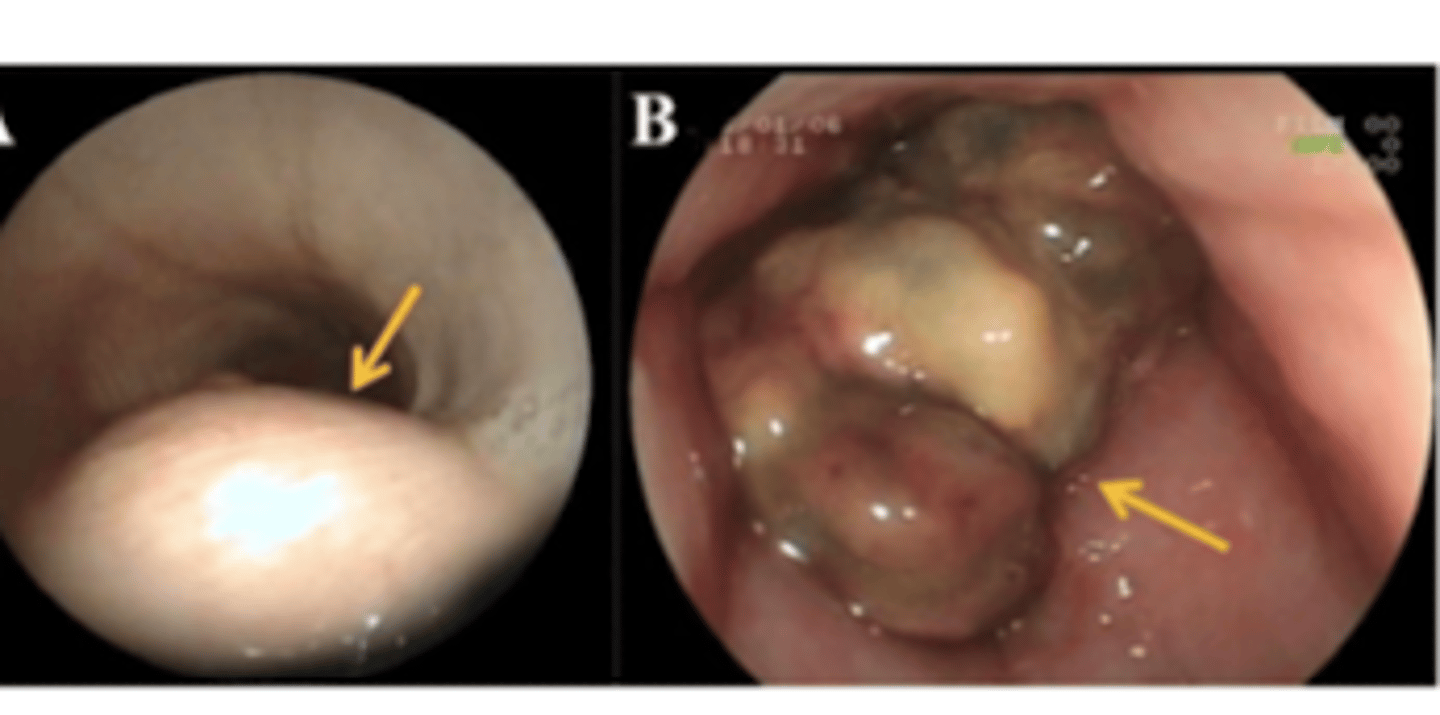

intramural esophageal stenosis

what is the name of this disorder?

the narrowing of the esophagus due to the thickening of the esophageal wall (ex: scar tissue)

intraluminal esophageal stenosis (due to a foreign body)

what is the disorder we see here?

neoplasia in the esophagus

what is the problem we see here?